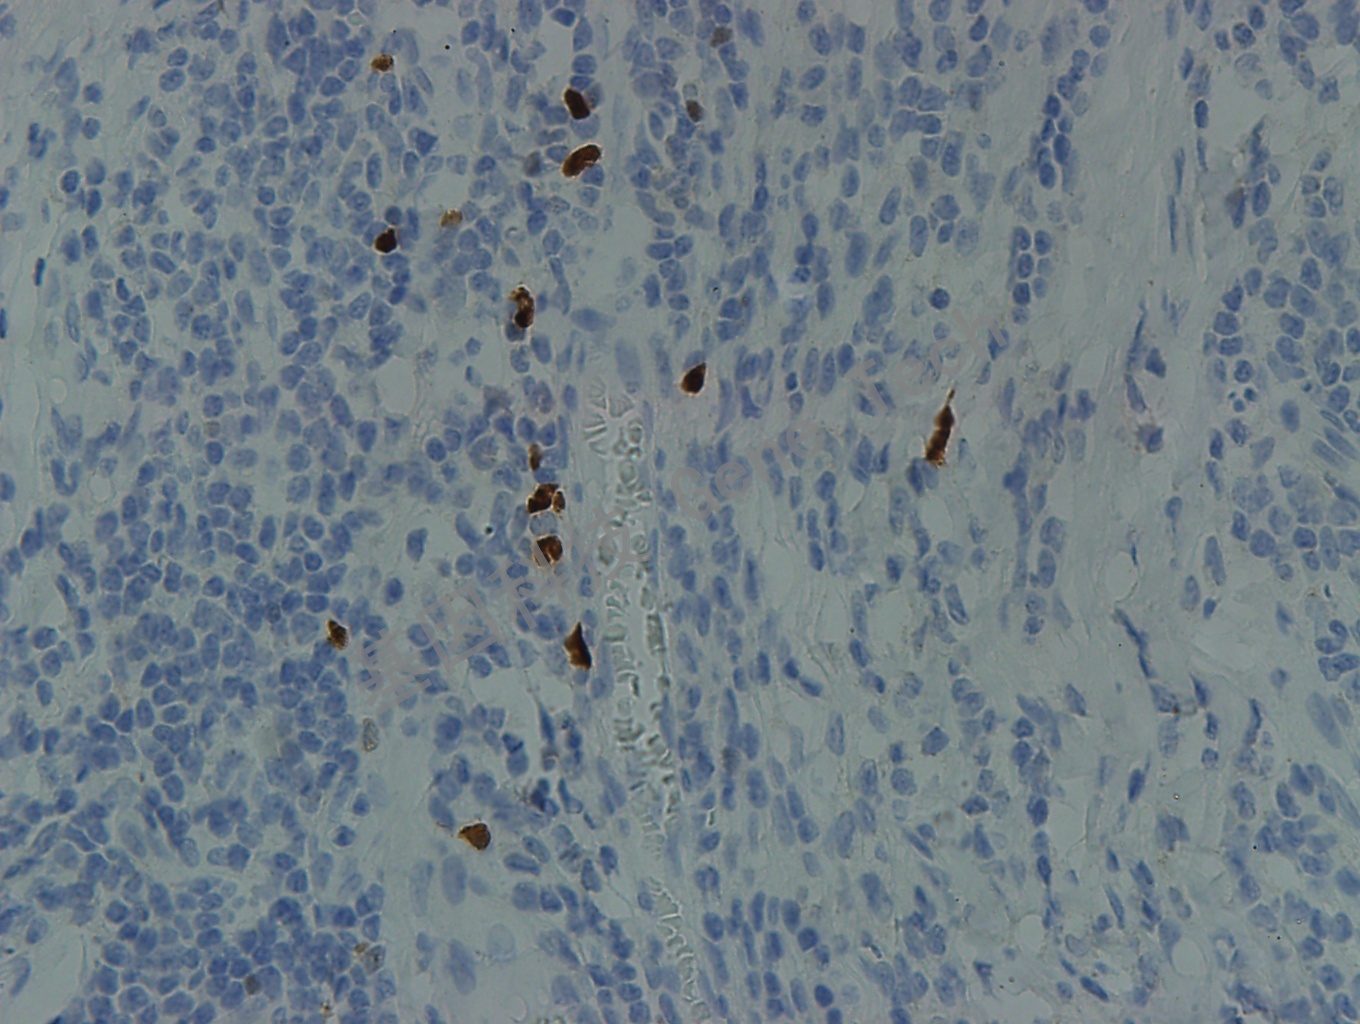

扁桃体石蜡切片,用 TdT(GT2025)染色,细胞核阳性,DAB 显色。